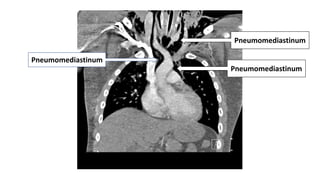

To The Neck…

Gunshot Wound

Injury To The Trachea & Esophagus

Pneumomediastinum